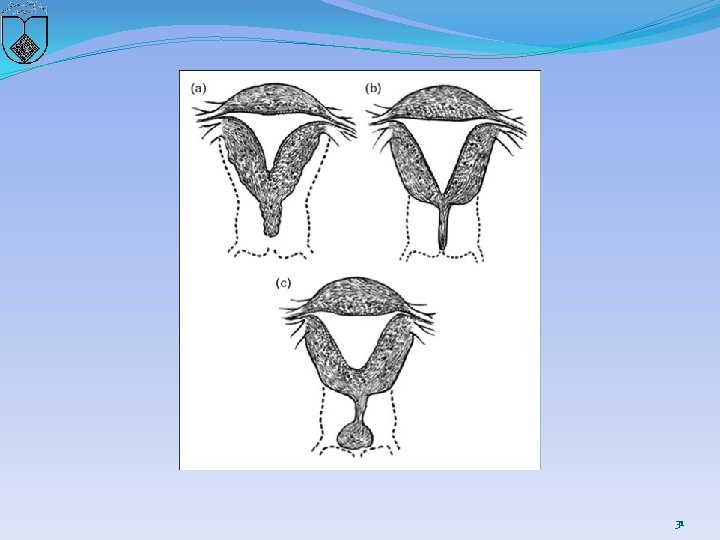

Two basic categories of cervical anomalies �first type: � cervical aplasia, lack a uterine cervix �lower uterine segment narrows: terminate in a peritoneal sleeve at a point well above the normal communication with the vaginal apex 30

�second type, cervical dysgenesis (1) Cervical body consisting of a fibrous band of variable �length and diameter (endocervical glands may be �noted on pathologic examination; (2) Intact cervical body with obstruction of the cervical �os (cervical ostium; the cervix is usually well formed, �but a portion of the endocervical lumen is obliterated; (3) Stricture of the midportion of the cervix (which is �hypoplastic with a bulbous tip and no identifiable �cervical lumen; (4) Fragmentation of the cervix (with portions that can �be palpated below the fundus and that are not connected �to the lower uterine segment 32